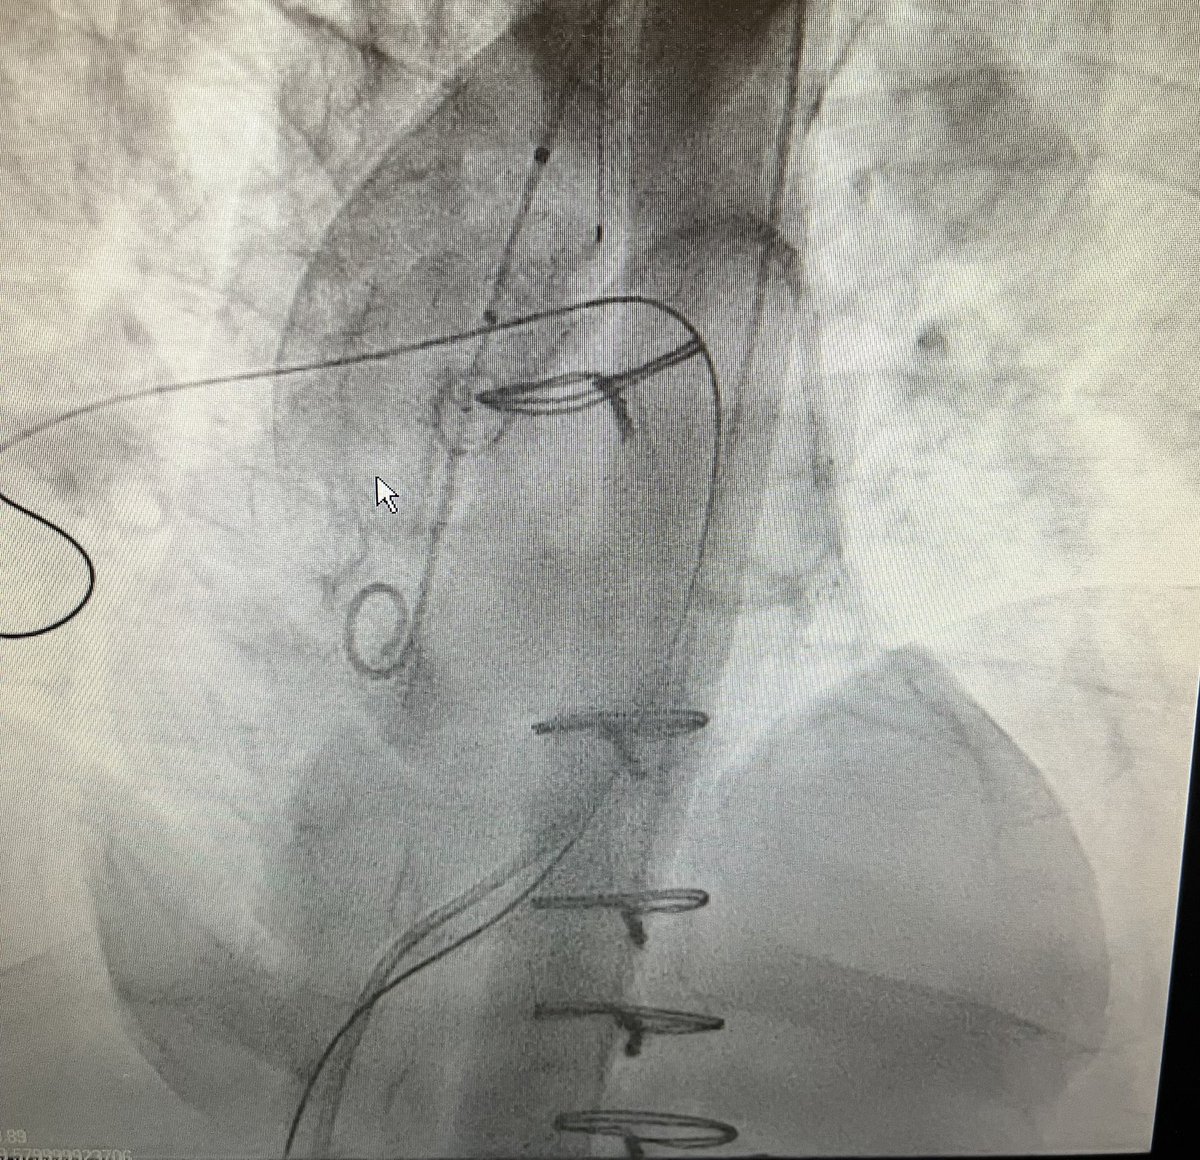

This @CASEfromASE's objective is to highlight the value of advanced cardiac imaging to guide patient management and facilitate advanced percutaneous interventions to reduce morbidity and mortality in patients with #ACHD. bit.ly/4ca7729 #CASESpecialIssue #10DaysofCASE